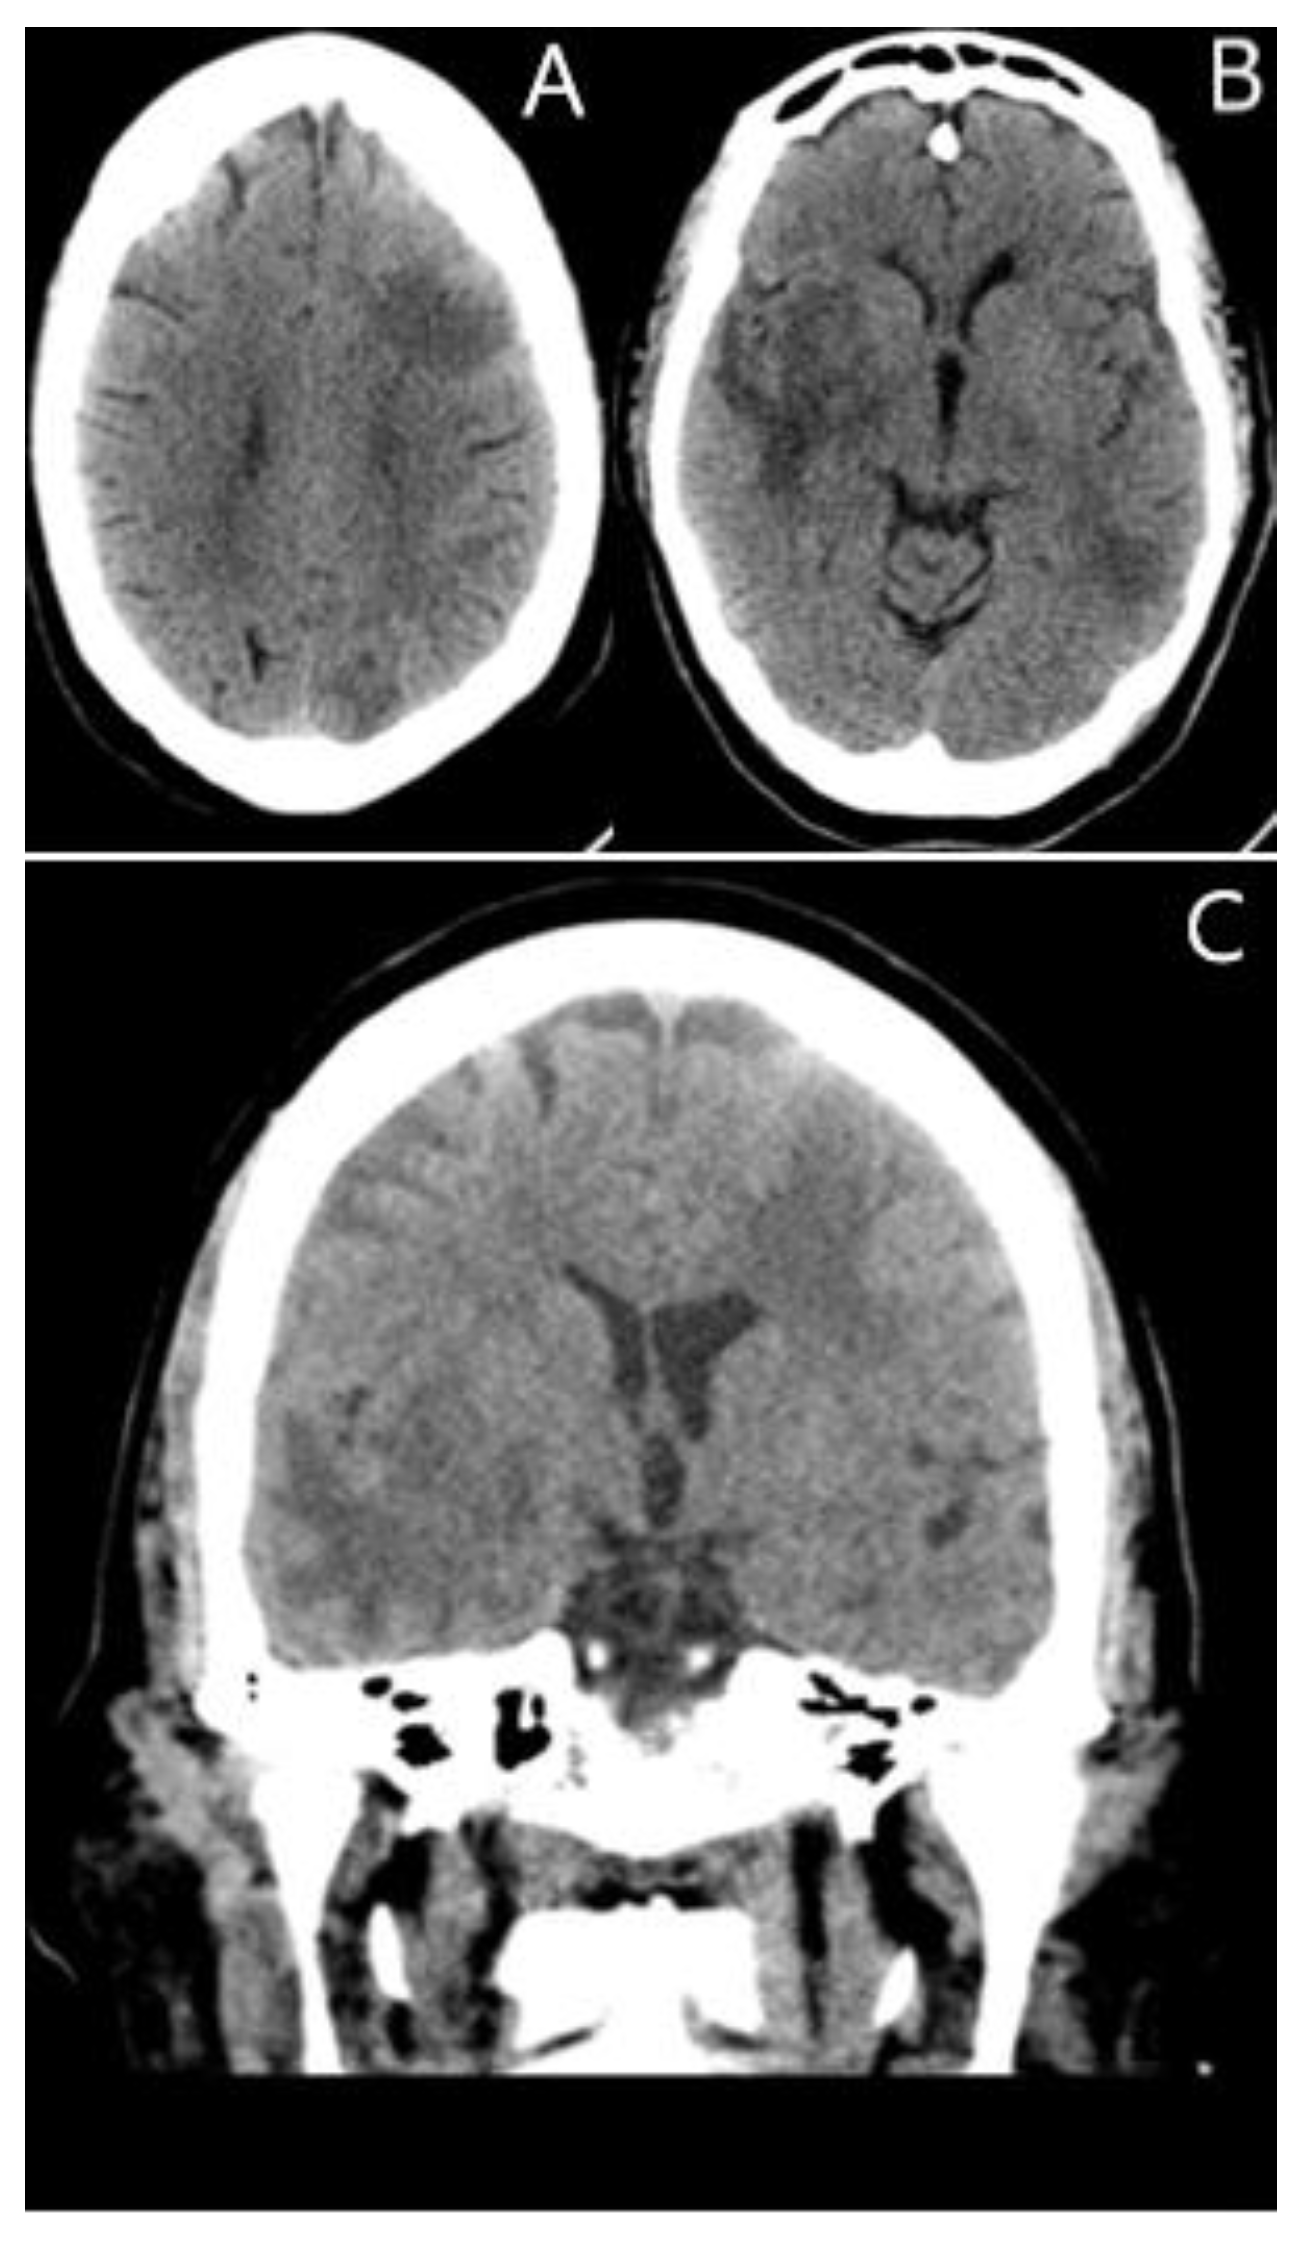

2. Case Presentation